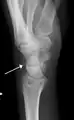

Triquetral avulsion fracture

Triquetral fractures can occur due to forceful flexion of the wrist, causing an avulsion of the dorsal aspect of the bone that is often hidden on anterior radiographs, but can be seen as a tiny bone fragment on lateral views.

Treatment is generally by casting for 4 to 6 weeks.[3]